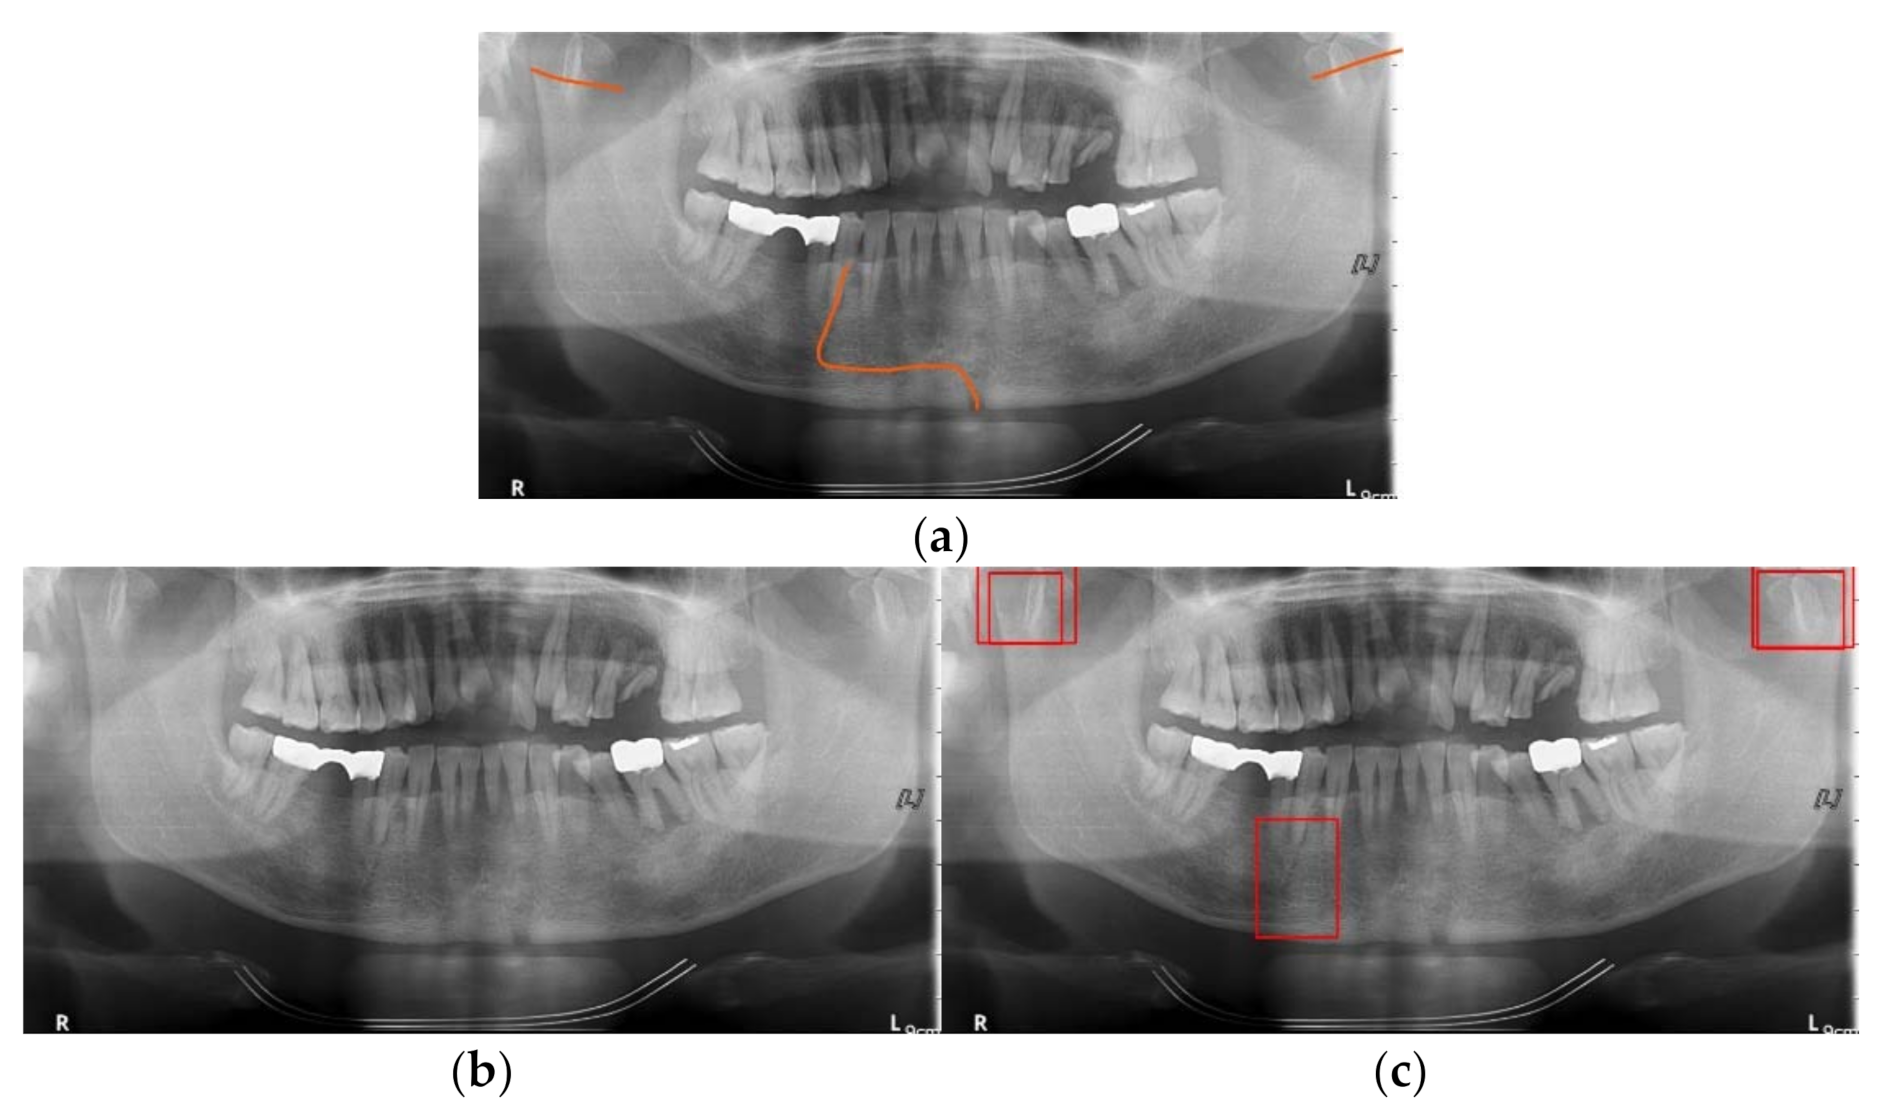

3.2. Detection Results